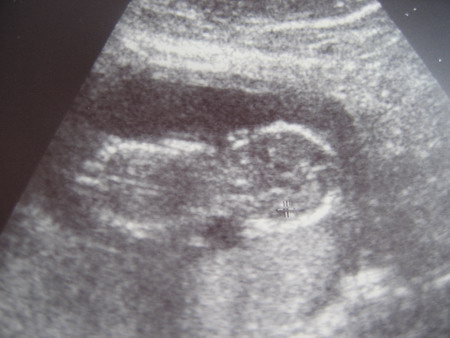

Ő pedig a picink, akinek feltűnően nagy fülei vannak, még az uh-képen is látszik :lol: Lehet, hogy jobb lenne, ha nem lány lenne, de ezt csak viccnek szántam :lol: 8 cm különben az ülőmagassága kb.

Kép